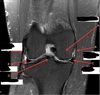

How well did you know this?

1

Not at all

2

3

4

5

Perfectly

Q

What is letter C?

A

INFRASPINATUS MUSCLE